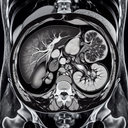

МРТ печінки

Магнітно-резонансна томографія (МРТ) печінки — це високоточний метод діагностики, який використовують для детального обстеження печінки та навколишніх тканин. Ось як зазвичай проходить ця процедура в приватній клініці: 1. **Підготовка:** - Пацієнта можуть попросити утриматися від їжі протягом кількох годин до обстеження...